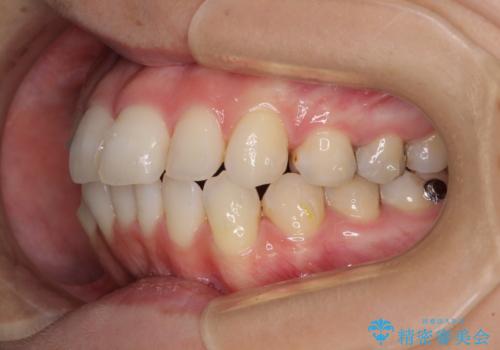

- 前歯のデコボコを気にして来院された患者様です。

主に下顎歯列全体の後方移動とIPR(歯と歯の間を削る)によってデコボコが解消するように設計し、インビザラインにより治療を行うこととしました。

舌突出癖がある方ですと、叢生が解消すると同時に前方に拡大されてしまいますが、ゴムかけをしっかりと行ってくださったこともあり、スッキリとした仕上がりとなりました。